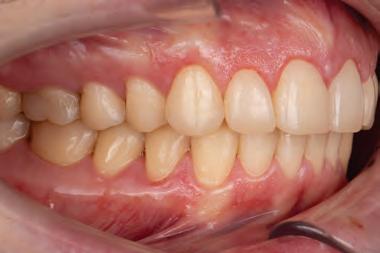

A 31-year-old woman presented with cosmetic concerns regarding her smile and requested a conservative enhancement. After clinical and radiographic analysis, digital 35mm photographs were taken and reviewed by the restorative clinician, technician, and surgeon (Fig 1). A digital impression was taken of the maxillary and mandibular arches using an intraoral scanner (Trios 3, 3Shape; Fig 2), and a smile design was developed with NemoSmile Design 3D software (Nemotec; Fig 3a). This allows for a facially driven smile frame to be created using reference lines of facial and smile proportions and natural teeth shapes and textures from the digital library (Fig 3b).

After developing the simulated mock-up, a 3D-printed resin model was created using CAD software (Fig 4a), and a clear PVS matrix (Exaclear, GC America) was fabricated to replicate the printed diagnostic wax-up using a nonperforated tray (Fig

Fig 1 Preoperative clinical views of a 31-year-old woman presenting with diastemas and limited tooth visibility. (top) Portrait. (center row) Intraoral views. (bottom row) Smile.

4b). This matrix was used to create an intraoral motivational mock-up with bis-acryl composite (Luxatemp Ultra, DMG). This additive mock-up provides the interdisciplinary team with an intraoral translation for evaluation (Fig 5). Upon evaluation of the digital smile frame and the clinical translation, it was determined that multiple esthetic and restorative requirements were necessary for an optimal biologic framework, and the interdisciplinary team determined the best sequence for these procedures. The patient was presented with the interdisciplinary treatment possibilities that included restoring the maxillary anterior teeth and premolars with a minimally

invasive preparationless procedure or with less conservative veneer preparations. The restorative materials discussed included injectable resin composites and ceramic (ie, feldspathic, pressable, machinable). For an optimal biologic framework and health, it was determined that connective tissue grafting would be necessary for treatment of the recessiontype defects on the maxillary left central and lateral incisors, canine, and premolars. The patient opted for the conservative preparationless composite veneers using the injectable resin technique followed by a connective tissue surgical procedure using the tunneling technique.